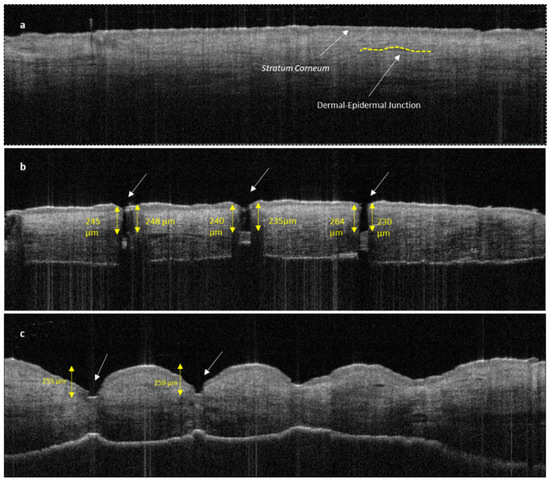

The disruption of the stratum corneum and the penetration into dermal layer by SMNs can be clearly seen in Figure 10b compared with untreated human skin (Figure 10a). The penetration of the sharp SMNs is highly perpendicular to the skin layers and creates a narrow vertical insertion profile with minimal indentation and skin damage. In contrast, PMNs penetrate into the epidermal layer with a higher degree of indentation and skin deformation (Figure 10c).

Figure 10.

OCT image of untreated human skin (a); human skin treated with SMNs (b); and human skin treated with PMNs (c). Both images (b,c) show clear stratum corneum disruption. The length of MN insertions is approximately 230–250 μm for both SMNs and PMNs. PMNs caused significantly more indentation and skin deformation than SMNs. The white arrows indicate microneedle penetration points.